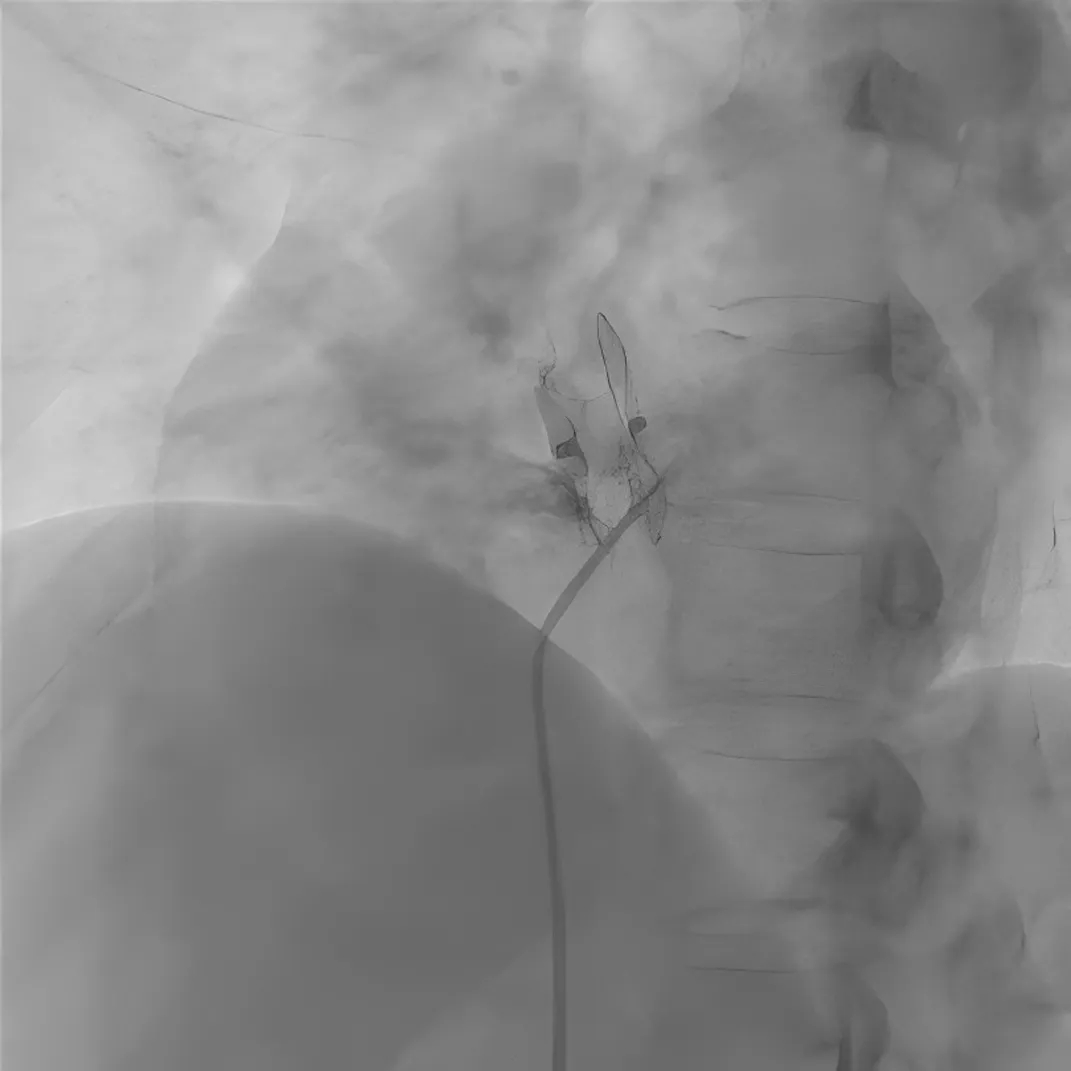

图2 选择性房间隔造影

造影显示原封堵器下缘存在残余分流